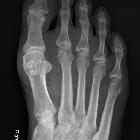

Ankylose

zwischen Sesambein und Metatarsale 1 Köpfchen. Die Häufigkeit einer solchen Verschmelzung wird mit ca. 4 % angegeben.